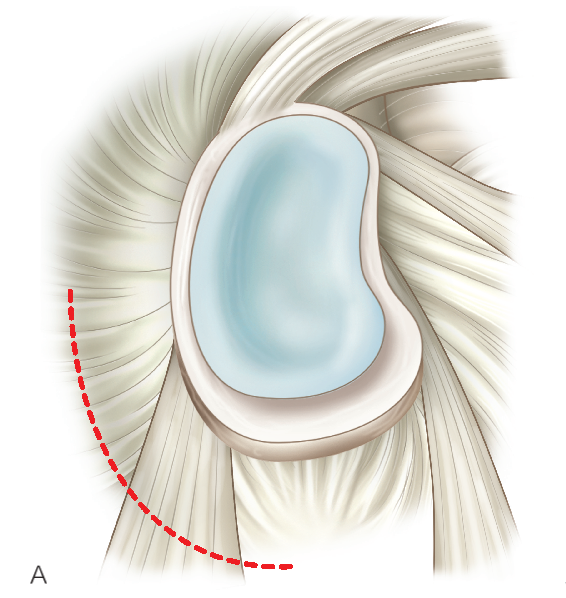

6 种手术入路

3. 低位前方入路:位于肩胛下肌腱上缘的正上方;用于锚钉置入、关节囊紧缩和前方盂唇修复或关节囊缝合的打结操作入路。

4. 前上入路:位于肱二头肌滑车前方,肩袖间隙的高位;上盂唇修复的锚定置入;SLAP 修补打结;修复前方盂唇和探查后方盂唇和关节囊。

5.Wilmington 入路:后上方关节盂锚钉的置入,后上方盂唇穿线过线。

6. 后外侧入路(7 点钟位置):辅助入路,用于对后方盂唇进行锚钉置入和修复。

P,后方入路:首先建立,是主要的探查入路。 A,直接前方入路:主要的操作入路;多用途的;可用于诊断性关节镜检查,肩袖关节内面的清理及后方探查。 LA,低位前方入路:位于肩胛下肌腱上缘的正上方;该操作入路用于置入锚钉、关节囊紧缩,前方盂唇修复或关节囊缝合术的打结。 AS,前上方入路:位于肱二头肌滑车前方肩袖间隙的高位;用于从 11 点钟到 1 点钟位置上盂唇修复锚钉的置入;SLAP 修补打结;前方盂唇修复时理想的探查视野,或用于后方盂唇和关节囊的探查。 L,外侧入路:用于进入肩峰下间隙,肩袖修复。 7,后外侧入路(7 点钟位置):B 辅助入路用于后方盂唇锚钉的置入和修复。